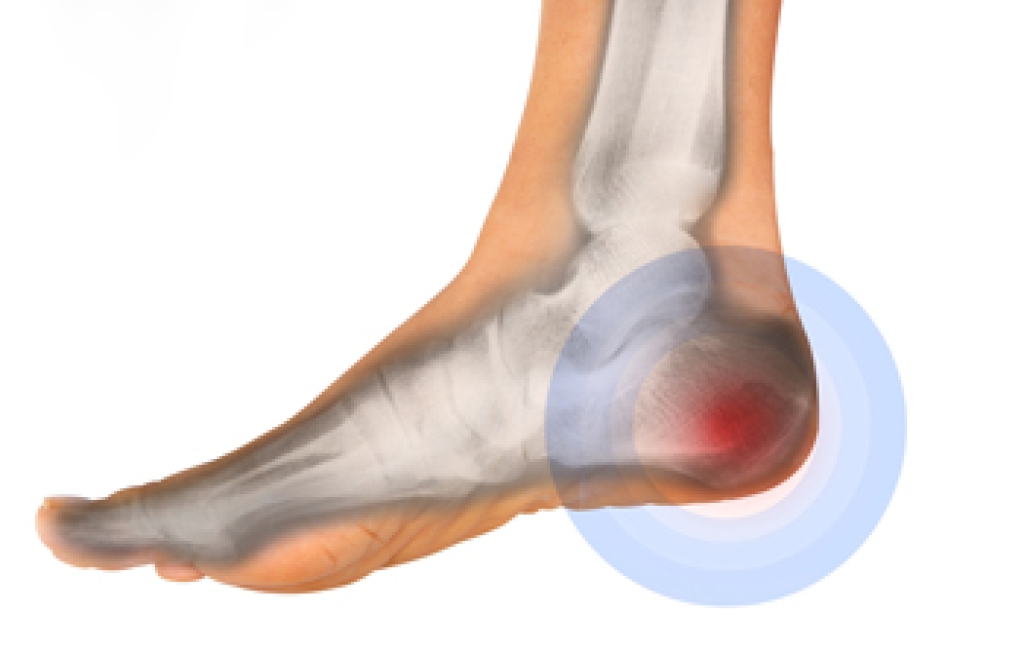

A Podiatrist’s Role in Relieving Ankle Pain

Ankle pain is discomfort that affects the joint connecting the foot and lower leg, an area that supports movement of the toes and calves while allowing stability during daily activities. Symptoms can include swelling, tenderness, changes in gait, deformity of the ankle, difficulty moving the ankle or toes, and an inability to bear weight. These issues may come from injury, arthritis, or structural problems. A podiatrist can evaluate the joint, provide a precise diagnosis, offer treatments that improve mobility, reduce pain, and prevent further injury. If you have ankle pain, it is suggested that you seek expert podiatric care to restore comfort and function, beginning your path to relief.

Ankle pain is any condition that causes pain in the ankle. Due to the fact that the ankle consists of tendons, muscles, bones, and ligaments, ankle pain can come from a number of different conditions.

The most common causes of ankle pain include:

- Types of arthritis (rheumatoid, osteoarthritis, and gout)

- Ankle sprains

- Broken ankles

- Achilles tendonitis

- Achilles tendon rupture

- Stress fractures

- Bursitis

- Tarsal tunnel syndrome

- Plantar fasciitis

Symptoms of ankle injury vary based upon the condition. Pain may include general pain and discomfort, swelling, aching, redness, bruising, burning or stabbing sensations, and/or loss of sensation.

Due to the wide variety of potential causes of ankle pain, podiatrists will utilize a number of different methods to properly diagnose ankle pain. This can include asking for personal and family medical histories and of any recent injuries. Further diagnosis may include sensation tests, a physical examination, and potentially x-rays or other imaging tests.

Just as the range of causes varies widely, so do treatments. Some more common treatments are rest, ice packs, keeping pressure off the foot, orthotics and braces, medication for inflammation and pain, and surgery.